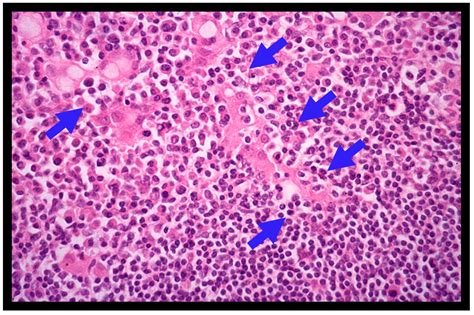

• Histopathological Examination: The biopsy samples are examined under a microscope to confirm the presence of MALT lymphoma cells. Immunohistochemical staining and molecular tests may also be performed to further characterize the cancer cells.